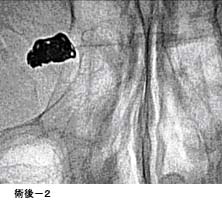

破裂脳動脈瘤に対するコイル塞栓術GODコイルだとちょっと古いので、コイル塞栓術とする方が良いのではないかと思います。

術後 コイルにより動脈瘤が写らなくなりました。